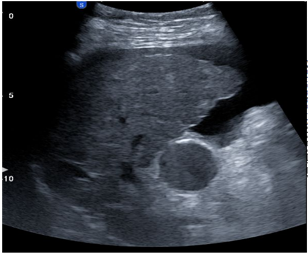

肝脏检查 B/A 非线性成像

显示组织非线性参数变化以分辨组织病理特性

从不同声功率的基波和谐波信号,计算局部组织的B/A值

使用血液的B/A值做参考

可以定量检测,对脂肪肝尤其敏感

非线性成像(B/A)检测脂肪肝和肝纤维化

穿透可达20cm以上,具备非常深远的临床意义

结合AI智能对脂肪肝的定量检测

使用训练好的肝纤维化分类网络作为迁移学习,建立CNN+MSVM模型进行脂肪 肝和正常肝分类